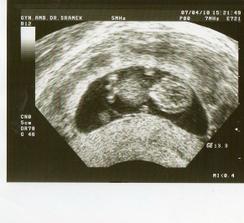

21.3. UTZ u doktora gyn. 9+3 tt. mimi má krásné srdíčko, ubrány prášky na miminum. další UTZ 30.3 v Gennetu.